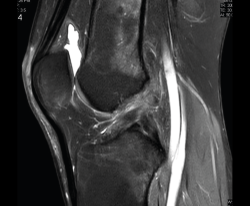

Resonancia magnética

Se basa en la propiedad que poseen los núcleos de hidrógeno de absorber energía electromagnética cuando están sometidos a un campo magnético intenso. La RM representa un mapa de la densidad de protones, o sea, de la distribución de agua por el organismo(12).

Se consiguen unas imágenes de alta resolución para la valoración de meniscos, ligamentos y tendones. Además, es especialmente útil en las rodillas operadas, lesiones tumorales, evaluación del cartílago y la visualización de los nervios(13).

1. Estudio de las estructuras intraarticulares

Es la prueba no invasiva de elección para valorar las lesiones internas de la rodilla(2). Aunque el estudio por RM es a menudo considerado como la prueba diagnóstica de elección para la detección de alteraciones meniscales, se asocia en ocasiones con errores diagnósticos(16).

1.2. Ligamentos

Se visualizan como estructuras lineales hipointensas en todas las secuencias.

1.2.2. Ligamento cruzado anterior (LCA) (Figuras 40, 41, 42, 43 y 44)

Figura 40. Corte de secuencia sagital T2 Fat-Sat de resonancia magnética de rodilla: ligamento cruzado anterior normal.

Figura 41. Cortes de secuencia sagital T2 Fat-Sat de resonancia magnética de rodilla: rotura central del ligamento cruzado anterior.

Figura 42. Cortes de secuencia sagital T2 Fat-Sat: rotura proximal del ligamento cruzado anterior.